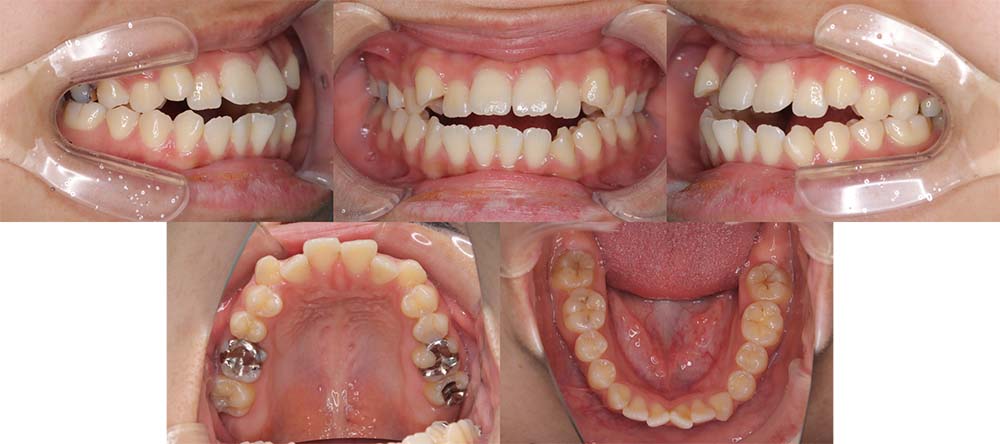

| 症例分類 | 上下顎前突、口唇突出 |

| 診断名 | 口唇突出を伴う上下軽度叢生 |

| 主訴 | 前歯が気になる |

| 年齢 | 15歳8ヶ月 |

| 性別 | 女性 |

| 抜歯部位 | 上下左右の第一小臼歯(4本) |

| 使用装置 | 表側のワイヤー装置 |

| 治療期間 | 1年9ヶ月 |

| 保定装置 | 固定式保定装置、取り外し式保定装置(8時間) |

| 費用 | [検査・診断料] ¥49,500 [基本施術料] ¥792,000 [調整料] ¥4,400/回 [抜歯] ¥5,500/本 [保定装置] ¥55,000(税込) 抜歯や虫歯治療は他院にて費用が別途かかります。(抜歯¥4,000〜10,000/本)

当初は前歯のガタガタを気にされており、上顎の部分治療を希望されました。しかしながら、上顎前歯の叢生のみの改善は可能だが、口唇突出感はなくなり、口が自然に閉じるようにするためには抜歯が必要なことを説明したところ、抜歯して治療することを希望されました。

上下第一小臼歯を抜去して表側のマルチブラケット装置で治療しました。顎間ゴムの協力度が良く予定より早く治療が終了することができました。

口唇突出感をなくし、しっかりと咬合することができました。